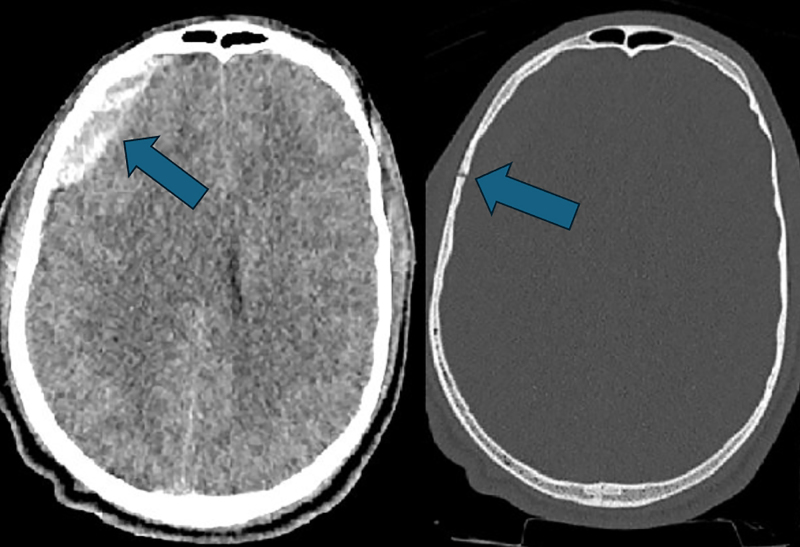

教学要点:神经源性肺水肿是脑外伤的一种罕见并发症,对于出现肺水肿的外伤患者,如果找不到其他原因,则应考虑神经源性肺水肿。

Teaching point: Neurogenic pulmonary edema is a rare complication of cerebral trauma and should be considered in trauma patients presenting with pulmonary edema when no other cause is found.